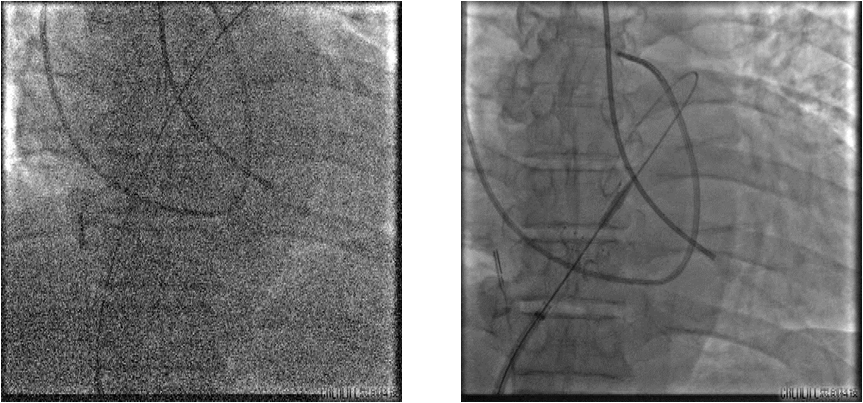

手术过程

FIM 研究